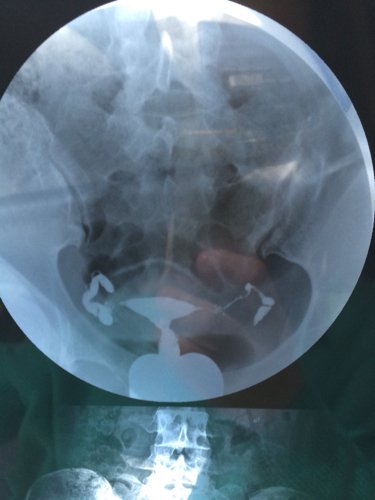

您好,医生。昨天我去做了一个子宫输卵管造影,结果检查所见子宫形态无明显异常。双侧输卵管伞部显影,双侧输卵管呈迂曲柔软的条状影。24小时后摄片示,造影剂在盆腔内积聚,弥散不良。检查结论双侧输卵管伞部碘油积聚,弥散不良,提示双侧输卵管伞部梗阻。请问医生我该怎么治疗,还有没有机会会人工受孕怀个健康宝宝呢?